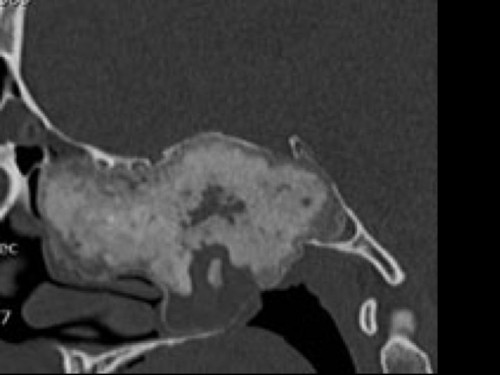

38 jähriger Patient. Seit neuestem Diplopie und immer wieder Kopfschmerzen. Seit er denken kann, vor allem beim Sport eine behinderte Nasenatmung.

Aus den CT Aufnahmen ist ersichtlich, dass ...

- Ader Tumor vom Clinoid ausgeht.

- Bes sich um einen gutartigen Tumor handelt.

- Ces sich um einen bösartigen Tumor handelt.

- Dder Tumor ossifiziert ist.

- Eer schon nach intrazerebral vorgewachsen ist.

Bildgebung - CT axial